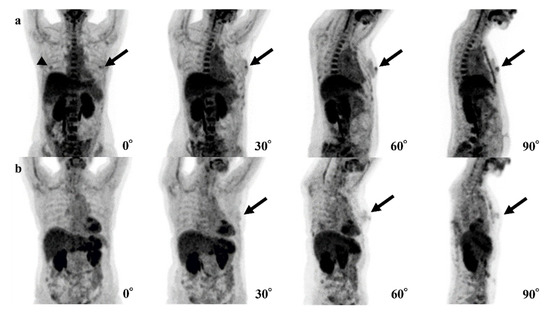

| Case | Age | SUVmax | Breast Density | Size of Invasive Components (mm) | Total Tumor Size (mm) | Pathology and Subtype | ER | PgR | HER2 | Ki67 |

|---|---|---|---|---|---|---|---|---|---|---|

| 1 | 44 | 2.0 | Heterogeneously | 11 | 11 | IDC | + | + | - | 9.1% |

| 2 | 70 | 0.9 | Scattered | None | 0.6 | DCIS | + | - | + | 15.4% |

| 3 | 70 | 1.2 | Heterogeneously | None | 8 | DCIS | + | + | + | 12.0% |